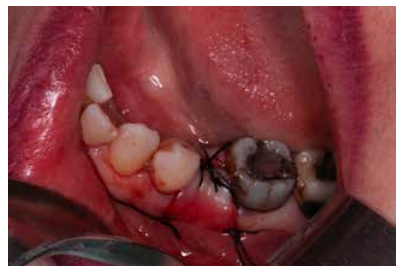

Materials and methods: A study was carried out on 6 patients from the Faculty of Dentistry of the Complutense University of Madrid performing the technique of alveolar ridge preservation. Two groups were established, a test group in which the alveolar socket was filled with calcium phosphate and added silicon and a control group where the socket was filled with bovine hydroxyapatite. After 3 months, a cone-beam computed tomography was performed to evaluate the bone density achieved by both biomaterials.